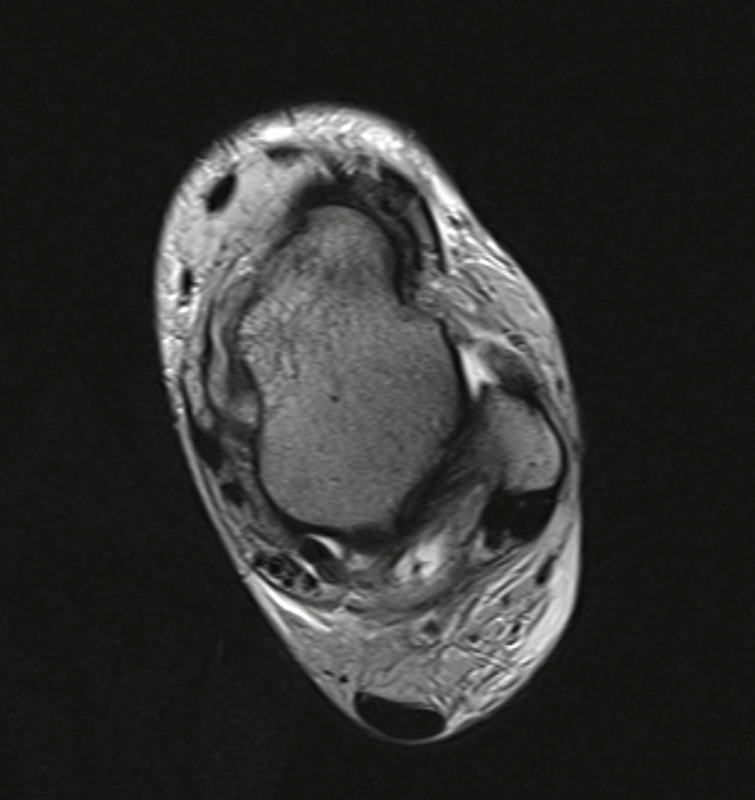

MRT

Die Kernspintomographie hat ihre Stärke in der Darstellung von Weichteilverletzungen. Insbesondere Verletzungen der Wachstumsfuge, des Periosts und der Bänder lassen sich gut visualisieren. Nachteilig ist die Untersuchungsdauer von 20-30 Minuten. Bleibt das Kind während dieser Zeit nicht ruhig liegen, kommt es zu Bewegungsartefakten, welche die Beurteilbarkeit der Bilder beeinträchtigen.

Os subfibulare

Multiple laminäre Ausrisse des fibularen Bandapparats aus der Fibulaspitze können zur Entwicklung eines Os subfibulare führen. Das Os subfibulare findet sich unterhalb der Fibulaspitze ventral der Peronealsehnen. Ohne Schmerzsymptomatik bzw. Aktivierung im MRT hat Das Os subfibulare keinen Krankheitswert. Ein mobiles Os subfibulare führt zu einer lokalen mechanischen Reizung teilweise in Verbindung mit einer Instabilität des Sprunggelenks. Im MRT zeigt sich eine Aktivierung des instabilen Areals. Bei anhaltenden Schmerzen besteht die Behandlung in einer operativen Entfernung des Knochens mit Refixation des Kapselbandapparats.